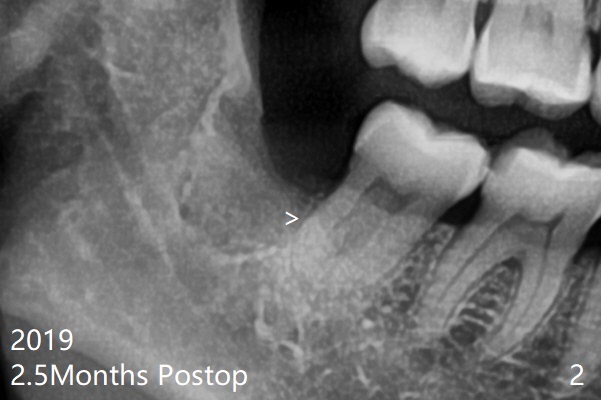

术后2.5月第二,三磨牙之间牙槽嵴薄(图二:>),术中破坏少